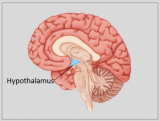

La neuroanatomie est la branche de l'anatomie qui étudie l'anatomie du système nerveux, c'est-à-dire la structure, la fonction et l'organisation du système nerveux.

Le système nerveux est l'un des systèmes les plus complexes du corps humain, et il comprend le cerveau, la moelle épinière, les nerfs périphériques et les ganglions nerveux. La neuroanatomie s'intéresse à la manière dont ces structures sont reliées les unes aux autres, comment les signaux sont transmis entre les cellules nerveuses, et comment les différentes parties du système nerveux travaillent ensemble pour contrôler les fonctions corporelles et cognitives. Les neuroanatomistes utilisent des techniques d'imagerie avancées, comme l'imagerie par résonance magnétique (IRM), la tomographie par émission de positons (TEP) et la microscopie pour visualiser les structures et les fonctions du système nerveux.